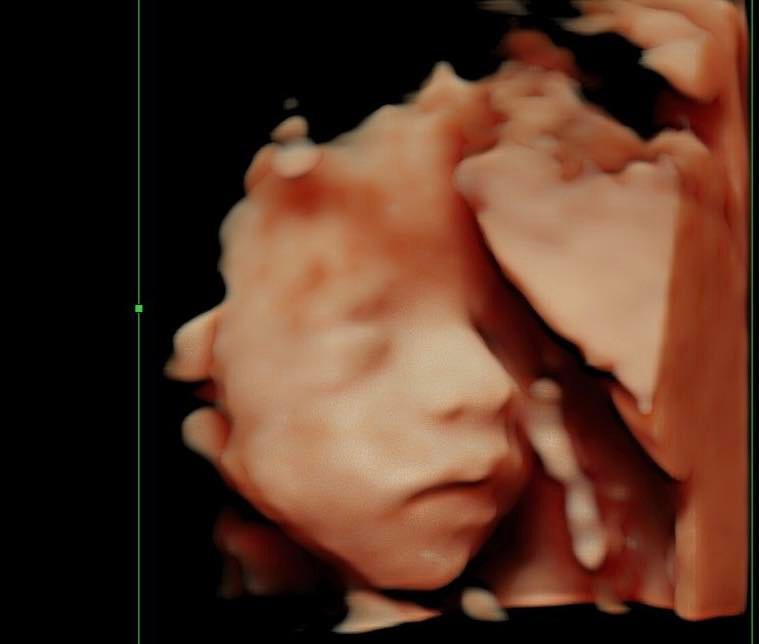

Không chỉ gây ấn tượng với những món ăn đậm chất miền Tây, Tiktoker Út Về Vườn còn khiến cộng đồng mạng bất ngờ khi khoe khả năng "nữ công gia chánh" cực kỳ khéo léo trong hành trình làm mẹ. Dù đang ở những tháng cuối thai kỳ với bụng bầu đã vượt mặt, cô vẫn kiên trì tự tay đan một chiếc nôi xinh xắn cho em bé sắp chào đời.

Trên trang cá nhân, cô chia sẻ hành trình đầy tâm huyết: "10 kg dây đan trong 10 ngày, mình làm được chiếc nôi cho em bé. Cách đây 1 năm đã tính làm chiếc xích đu bằng dây để treo trong nhà mà thấy được cái nôi bằng dây là mình mê liền, tự nhủ khi nào có em bé nhất định phải tự làm. Vậy nên từ ngày có bầu là đã nghiên cứu cách làm và mua đủ nguyên liệu nào là cột sắt, dây thừng, khung nôi, tấm lót bằng gỗ... có đủ đồ mình bắt đầu bắt tay vào làm".